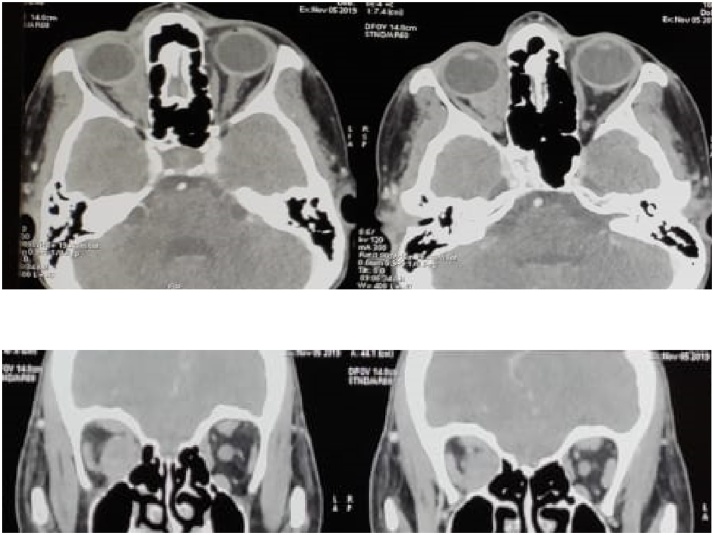

A facial computed tomography was performed showing a right orbital process at the expense of the internal rectus muscle. The patient underwent a surgical biopsy via the internal paracanthal approach in our department. Pathological examination of the surgical specimen confirmed the secondary origin of the process (Fig. 2).

Fig. 2.

Computed tomography of the orbits demonstrates a focal intraconal mass in the right eye englobing the medial rectus and optic nerve with indistinguishable borders.